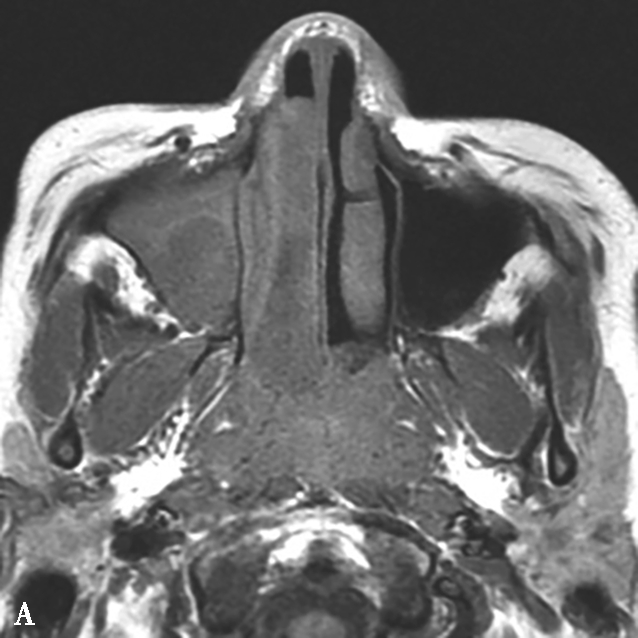

图1-3-20 慢性鼻窦炎

A~C.横断面、冠状面及矢状面CT平扫,示右侧额窦、上颌窦黏膜增厚,窦腔内可见软组织密度影,窦口鼻道复合体狭窄,右侧上颌窦窦壁骨质增生硬化、肥厚;D~F.同一患者横断面MR T 2 WI、T 1 WI及横断面增强T 1 WI,示右侧上颌窦黏膜增厚,呈T 1 WI等信号、T 2 WI高信号影,增强扫描示右侧上颌窦黏膜线样强化